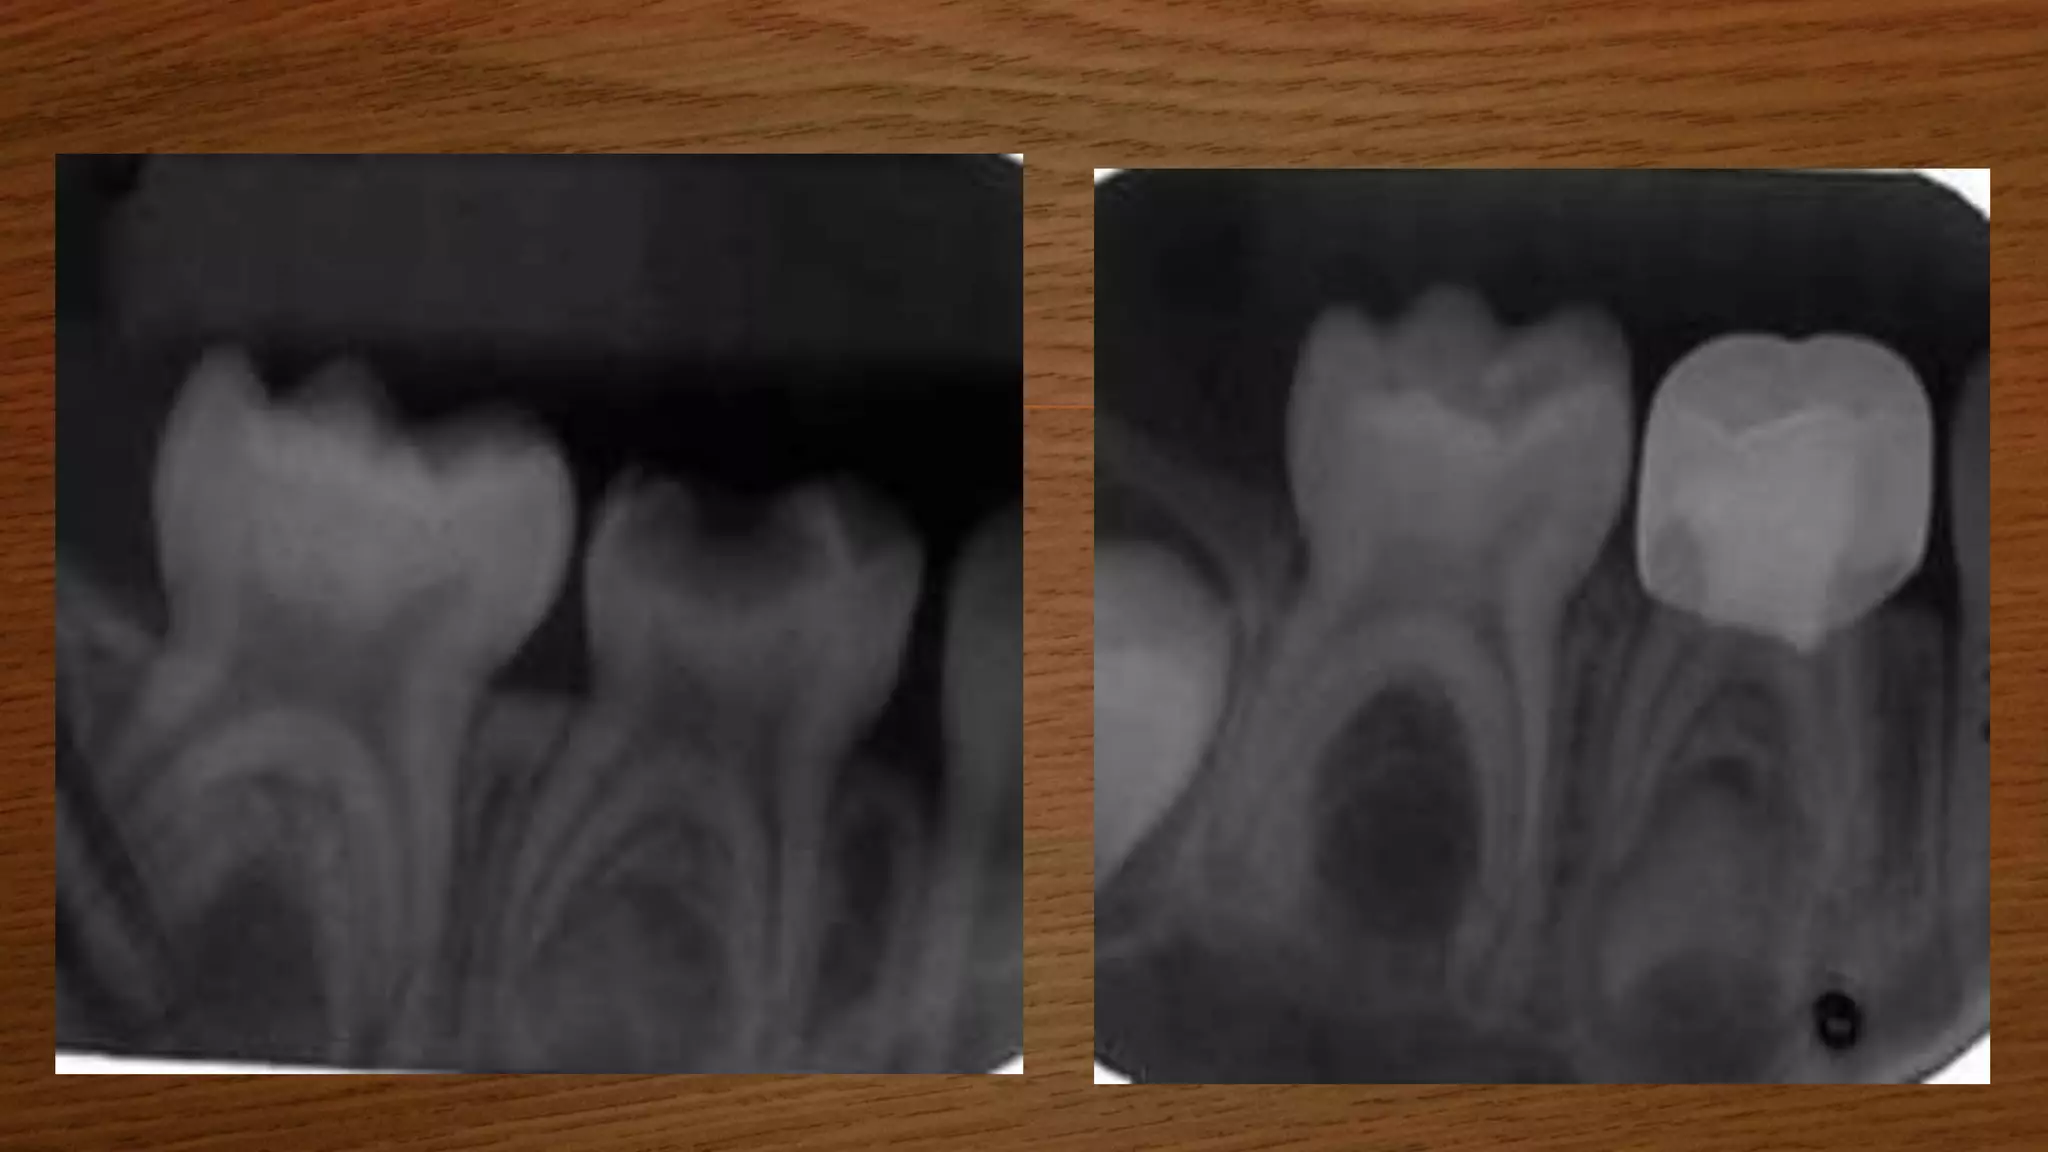

RADIOGRAPH

 BITEWING

 PERIAPICAL